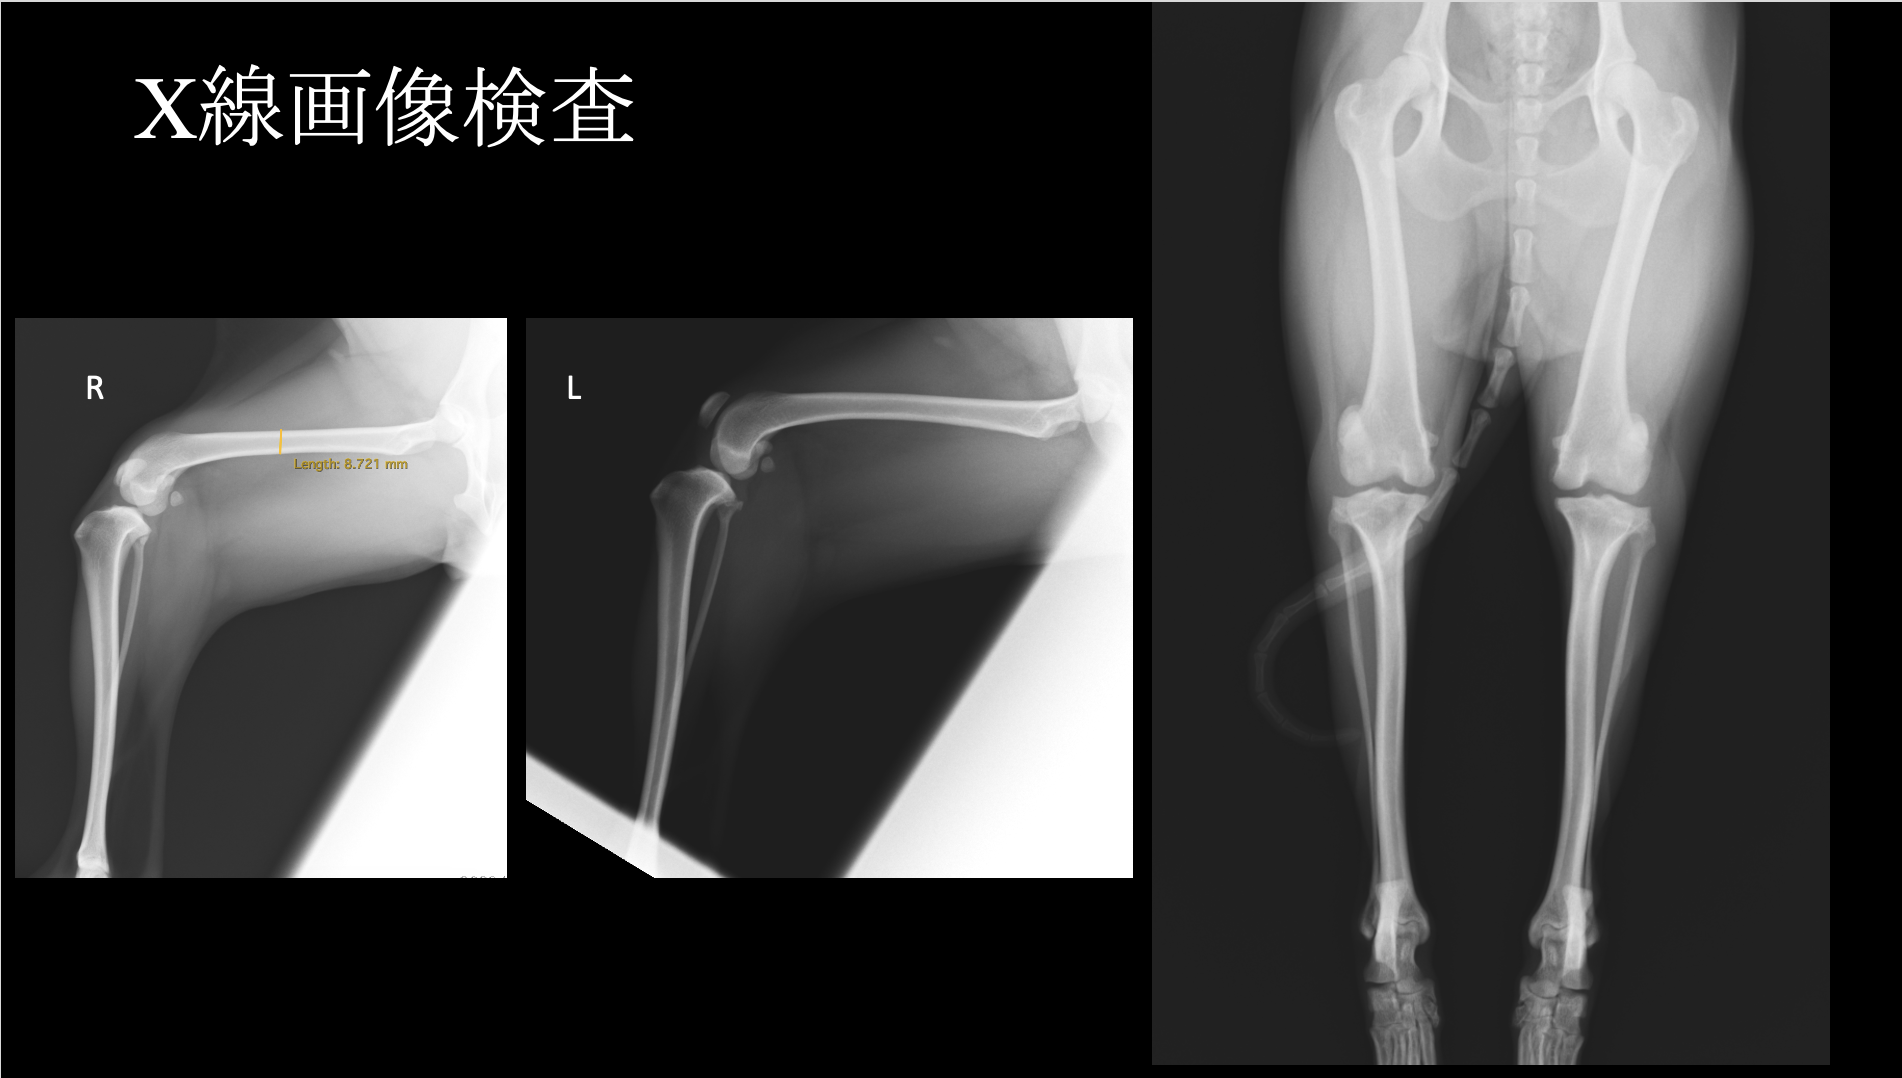

膝蓋骨外方脱臼(LPL)は小型犬では少なく、全体の10%以下と言われています。また、犬のLPLの治療は特に大型犬では成功率は非常に低いという報告があります。一方で、小型犬でのLPLの治療に滑車溝形成術、脛骨粗面転移術、軟部組織の手術を行なったところ、治癒率は高かったという報告もあります。現在のところ、小型犬膝蓋骨外方脱臼に対する報告は少なく、その治療方法は個々の獣医師の裁量に委ねられているところがあります。今回、小型犬の両側膝蓋骨外方脱臼(LPL)に対して、大腿骨前捻角矯正を行なったところ、治療が奏功した1例を紹介します。 症例はスピッツ、避妊雌、5歳1ヶ月齢、6.8kgです。既往歴は保護犬のため不明です。両後肢ともに曲がってしまっており、歩き方がおかしく、段差を降りることができないという主訴で来院されました。